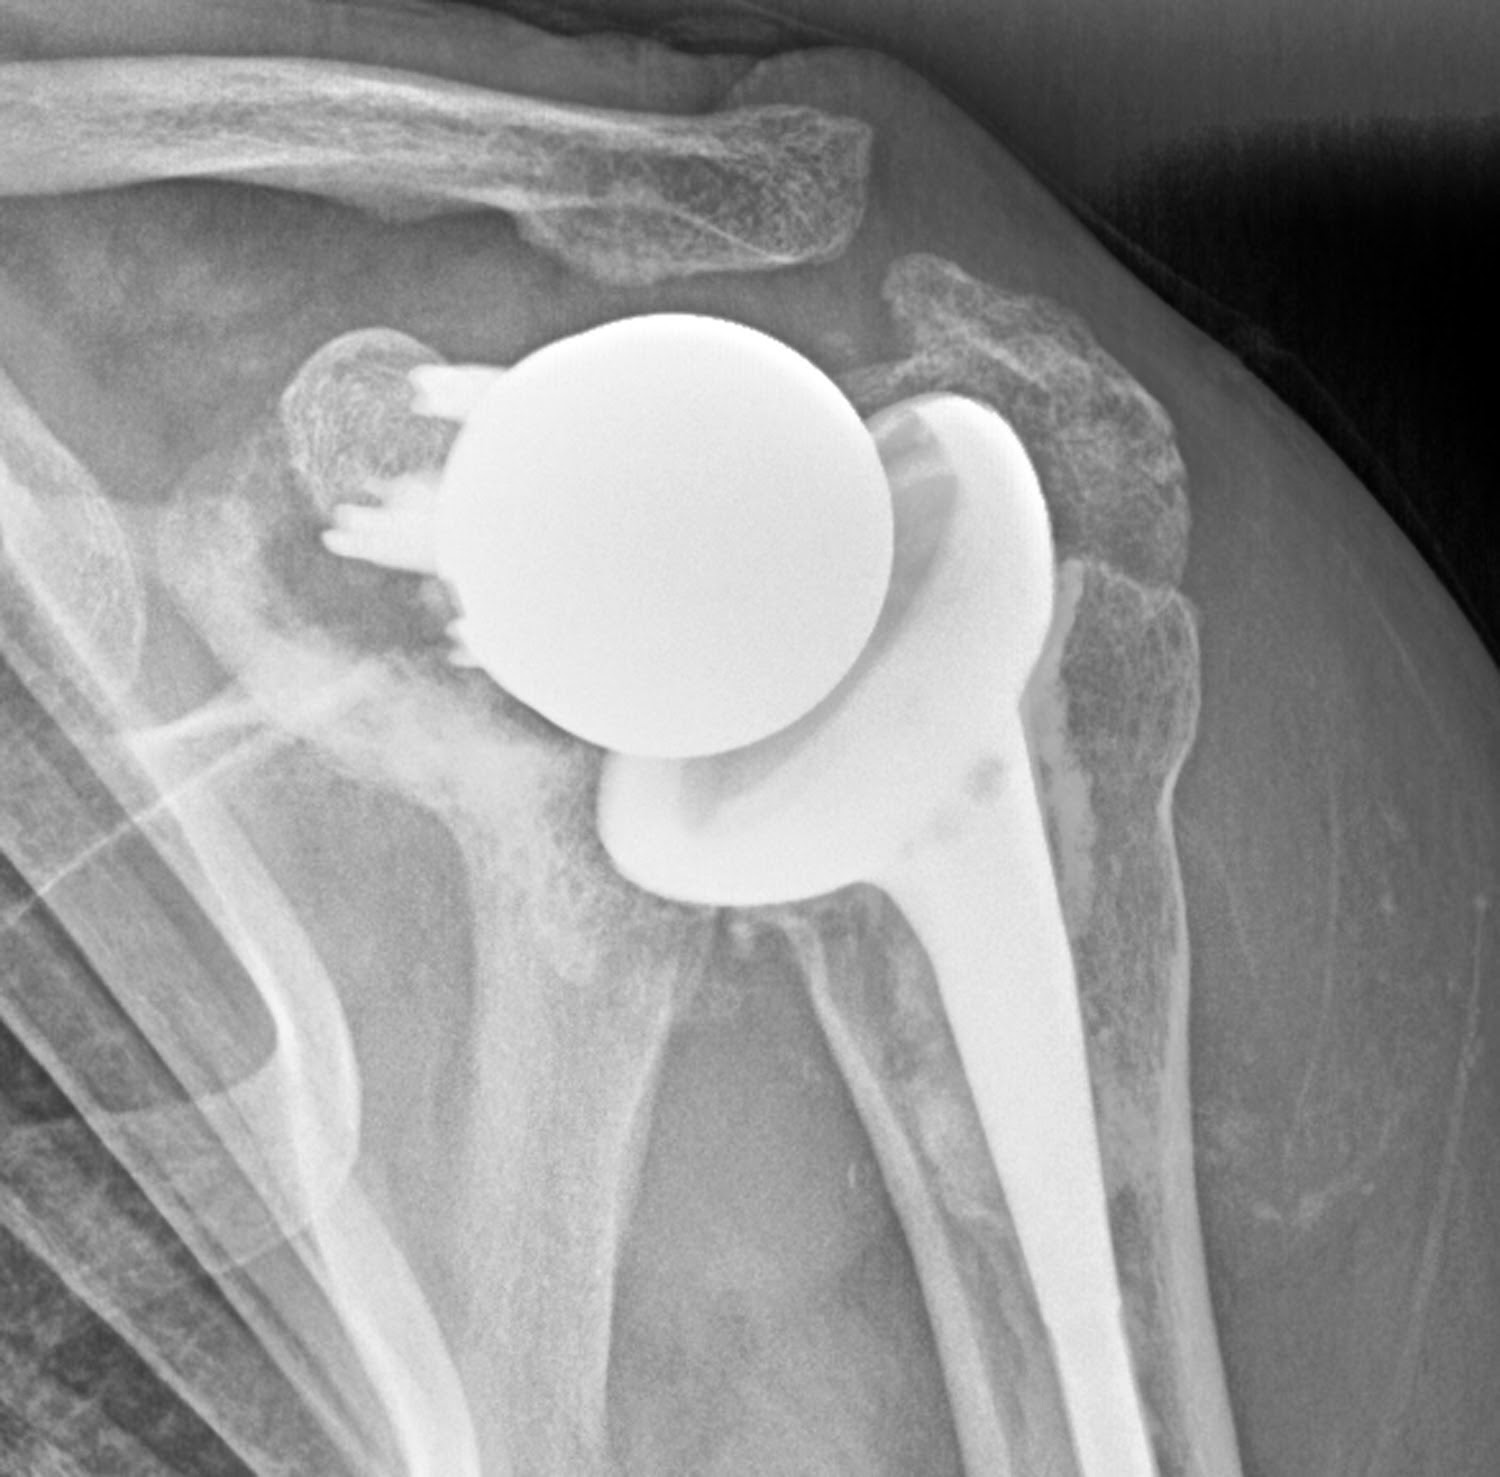

A Guide to Reverse Shoulder Replacement Surgery & Recovery

A Guide to Reverse Shoulder Replacement Surgery & Recovery Rotator Cuff Shoulder Joint Replacement The most common reason to consider a reverse prosthesis is when there is arthritis of the shoulder joint and the rotator cuff tendons are torn or gone. Total shoulder replacement is a complex procedure that involves replacing the shoulder joint with artificial parts. In a typical shoulder replacement, a plastic lining is attached to the socket to allow smooth movement.. Rotator Cuff Shoulder Joint Replacement.

UW Shoulder and Elbow Academy Reverse total shoulder joint replacement Rotator Cuff Shoulder Joint Replacement Total shoulder replacement is a complex procedure that involves replacing the shoulder joint with artificial parts. In these cases, a special kind of. The most common reason to consider a reverse prosthesis is when there is arthritis of the shoulder joint and the rotator cuff tendons are torn or gone. A shoulder replacement is a procedure that tries to eliminate. Rotator Cuff Shoulder Joint Replacement.